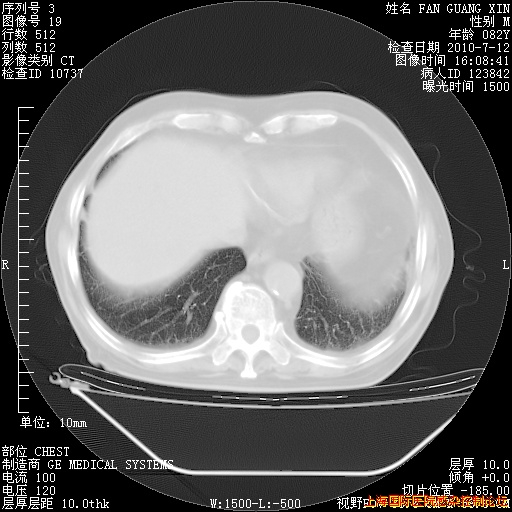

6月12日纵膈窗